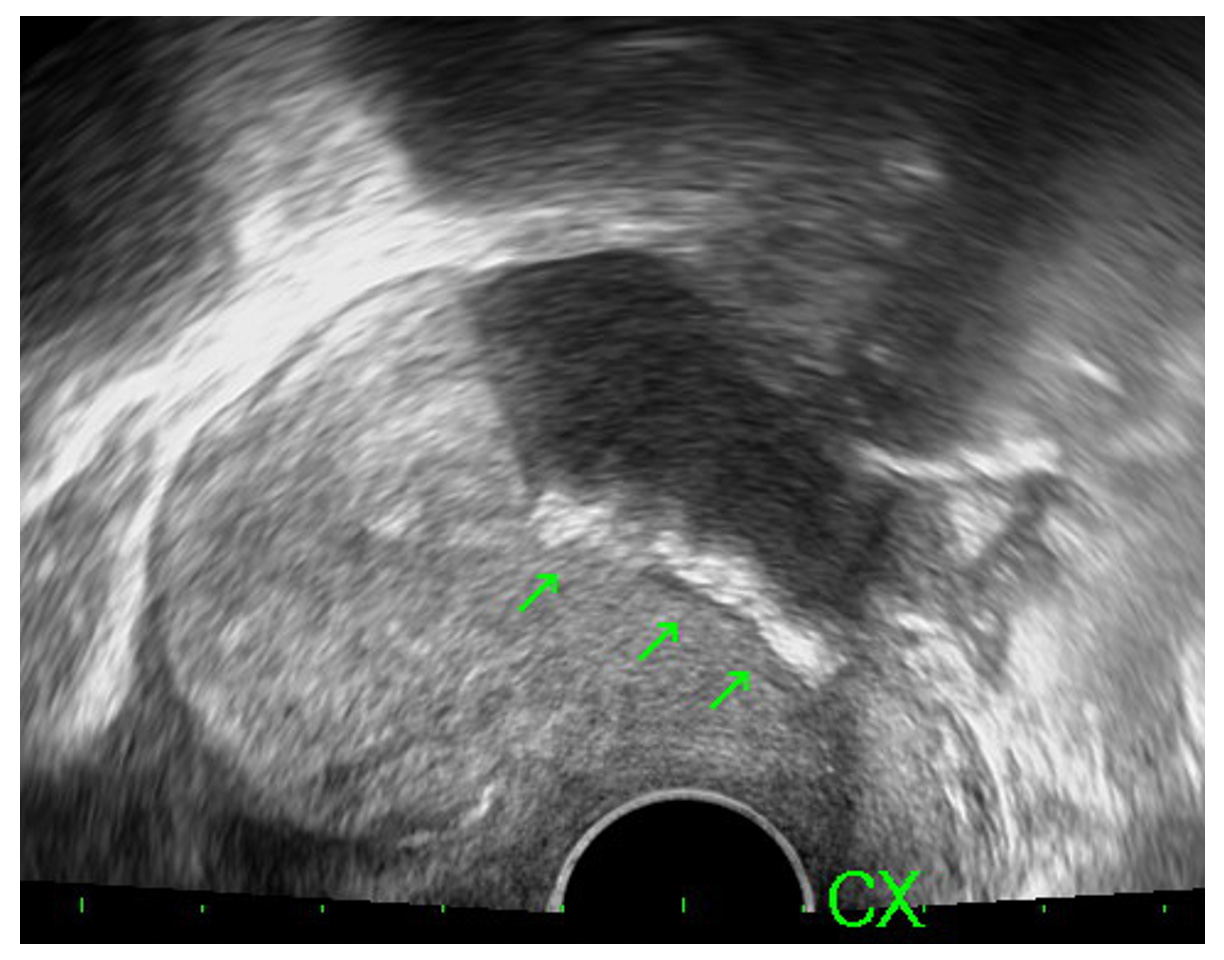

The first patient was a 32-year-old woman, gravida 3, para 2, who presented with persistent abdominal pain and malodorous vaginal discharge after surgery for three months. She had previously undergone hysteroscopic lysis of intrauterine adhesions at another hospital. Ultrasound revealed an irregular strip of hyperechoic lesion (length: 2.92 cm) located in the mid-portion of the uterine cavity and extending into the isthmus (Fig. 1). On diagnostic hysteroscopy, a foreign body presenting as a flattened bundle was seen within the uterine cavity (Fig. 2A). An operative hysteroscopy was performed to remove the extraneous material, which had a folded, multi-layered, film-like appearance (Fig. 2B). Her history revealed that a membranous AAB was applied in the uterine cavity during her previous surgery. Pathology confirmed chronic endometritis caused by a foreign body cell reaction with plasma cell infiltration in the endometrial tissue. The patient received postoperative metronidazole 500 mg every 12 hours for 3 days and was asymptomatic at 6-month follow-up.

Fig. 1.Ultrasound revealed an irregularly shaped strip of hyperechoic lesions (length: 2.92 cm) located in the mid-portion of the uterine cavity and extending into the isthmus.